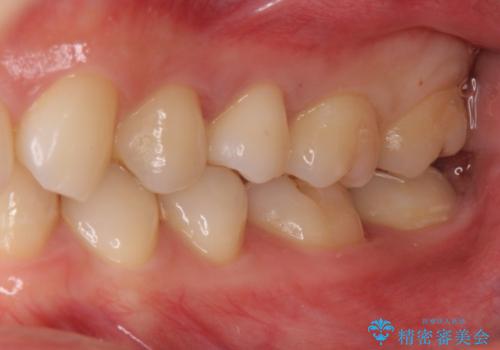

広げた後は歯が接するように修復するため、物が詰まることはありません。

- セラミックインレー:77,000万円、部分矯正:サービス(全体矯正を契約したため)費用は治療当時の料金となります